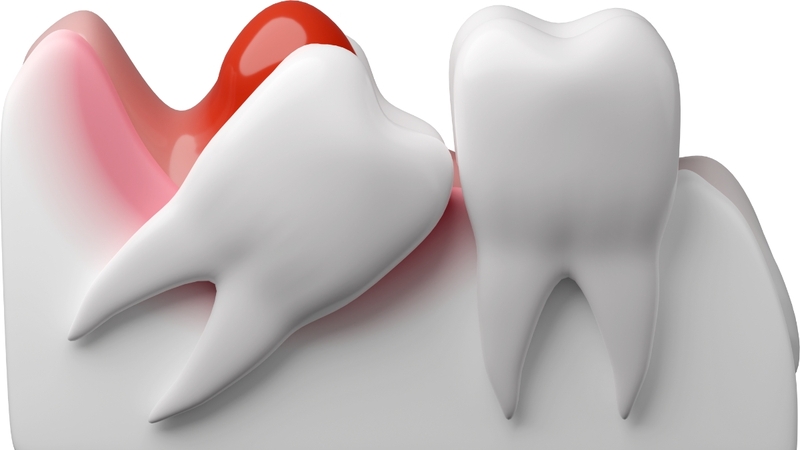

Răng khôn mọc lệch về phía gần

Đây là dạng mọc lệch phổ biến nhất, khi răng khôn có trục nghiêng về phía răng số 7 (răng hàm thứ hai). Sự nghiêng này làm cho bề mặt của răng khôn tì đè lên mặt xa của răng số 7, gây ra:

• Áp lực cơ học liên tục, dẫn đến tiêu chân răng hoặc tiêu men ở răng số 7.

• Tăng nguy cơ sâu răng kẽ do tích tụ mảng bám và khó vệ sinh.

• Viêm lợi trùm quanh răng khôn do phần thân răng chỉ mọc một phần ra khỏi nướu.

Răng khôn mọc lệch về phía gần là dạng mọc lệch phổ biến nhất, khi răng khôn có trục nghiêng về phía răng số 7